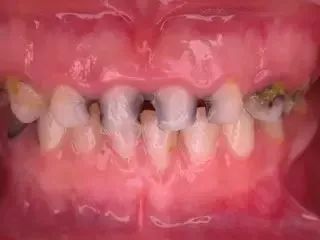

孩子的牙齿健康很重要,可他们自己却丝毫意识不到,所以妈妈们每天都在跟孩子斗智斗勇,想尽各种办法阻止他们吃糖,让他们养成良好的刷牙卫生习惯。即便如此,儿童龋齿率在我国依然居高不下。

窝沟是指口腔中磨牙上凹凸不平表面上的凹槽及沟隙,能够起到增大咀嚼面积、增加摩擦力的作用,有利于把食物充分嚼碎。而窝沟部位有时裂隙比较深,容易积聚致龋的细菌。孩子的刷牙方式通常仓促不认真,不易清洁到位,一旦细菌侵入牙齿就会发生龋坏,继而逐渐损坏整个牙齿,缩短牙齿的寿命。